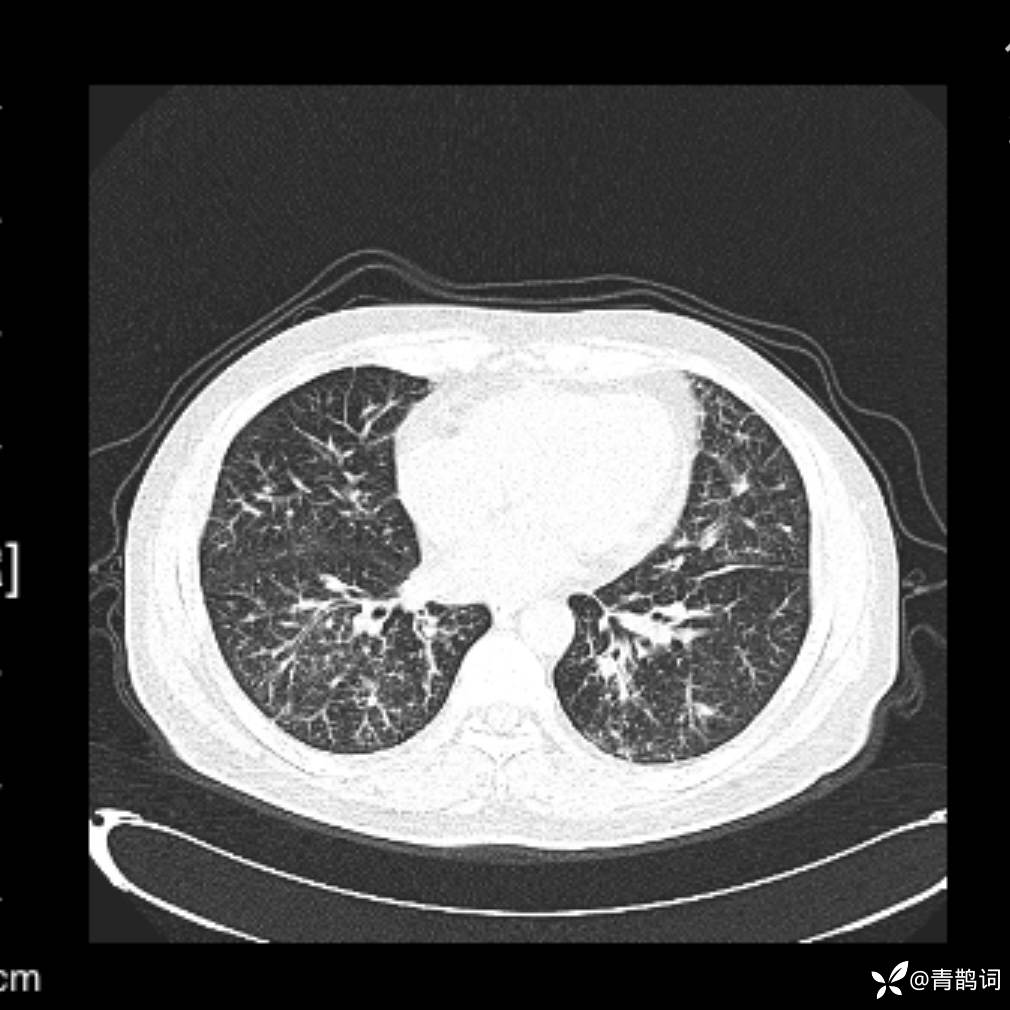

患者年龄:30岁。

患者性别:男。

简要病史:左颜面部肿胀2年,反复咳嗽咳痰,逐渐加重。

辅助检查

结合病史及影像学表现,期待评论区各位老师各抒己见~